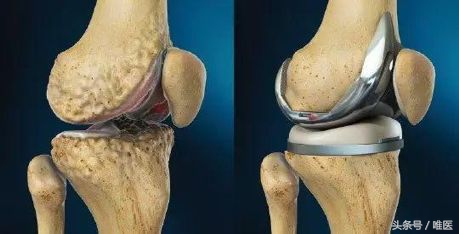

在临床中,总有一部分患者对于上述的保守治疗效果都不理想,这个时候,我们就需要通过手术来帮助他们解决问题。对于晚期的严重的膝关节骨关节炎而言,我们通常需要实行人工全膝关节置换术来帮助这些患者。人工全膝关节置换术是上个世纪出现的手术,也是现代骨科发展史上最为成功的手术之一,它能非常有效地根除晚期膝关节病痛,极大地提高病人的生活质量。目前,我国的人工全膝关节置换术开展已越来越普遍,成为了治疗晚期膝关节骨性关节炎的首选方法。

简单的说,这一手术就是将病变严重的膝关节股骨一侧和胫骨一侧的软骨和部分骨质以特殊的工具去除,然后根据每一个患者的膝关节尺寸选择合适型号的假体,用一种叫做骨水泥的粘合剂固定在膝关节内。通过这种手术,患者可以很快的正常行走和进行日常生活工作。